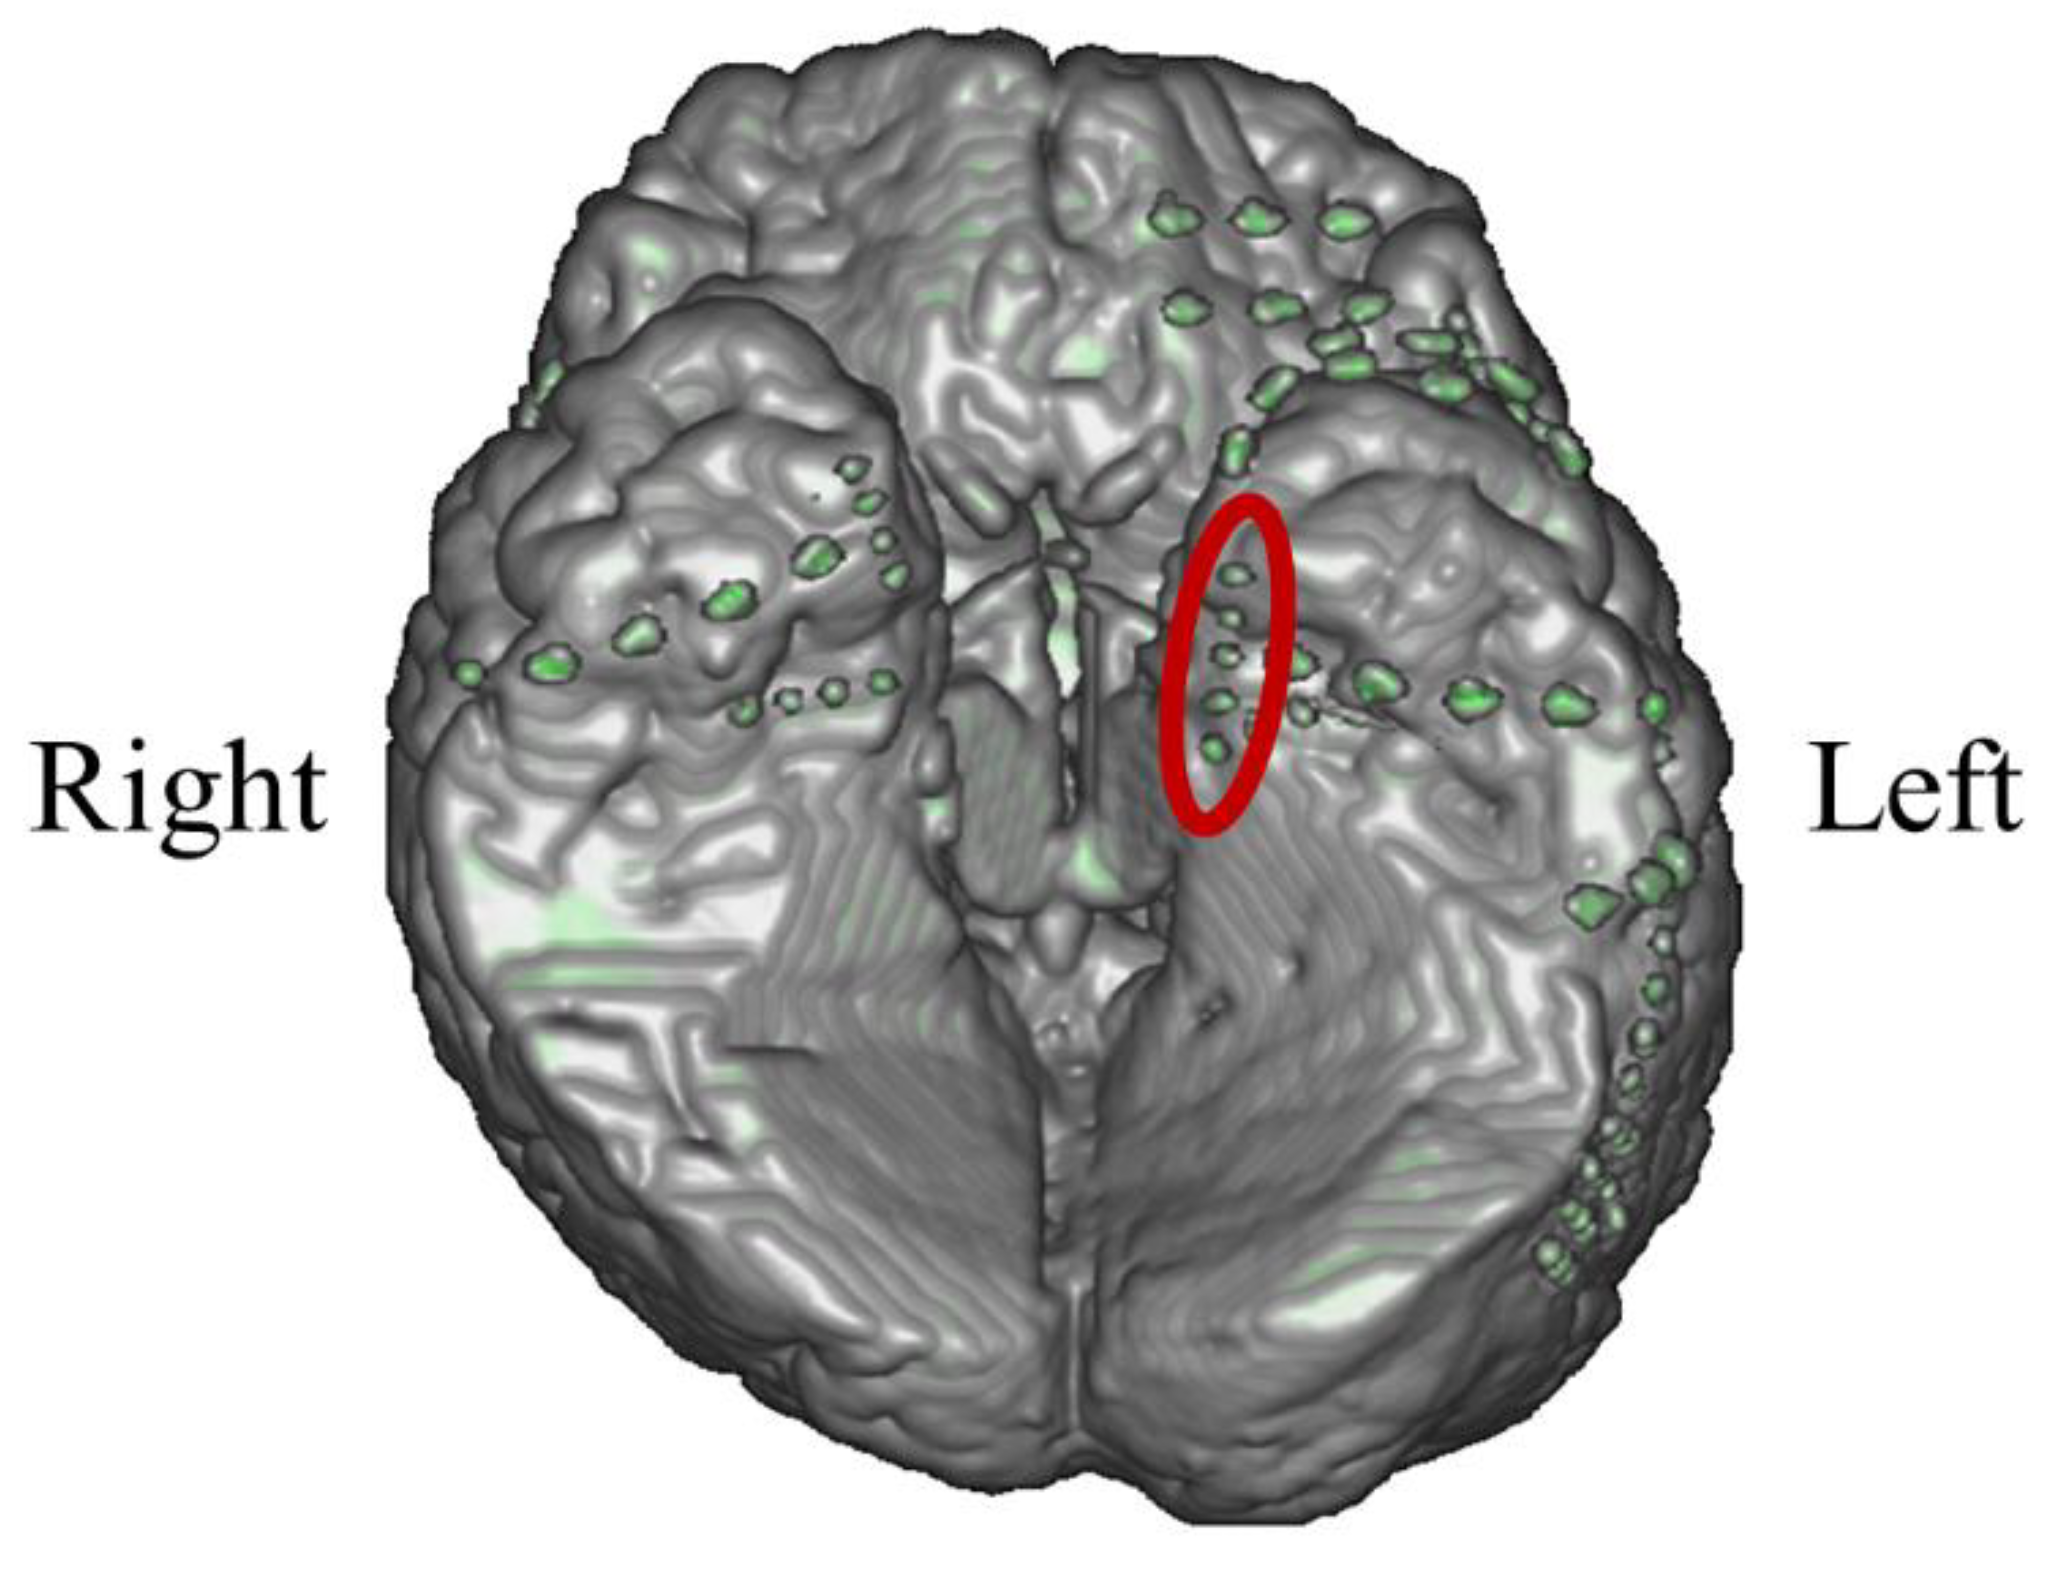

3.3.1. Intracranial Electrodes Used for Memory NF (P03)

In P03, subdural electrodes (Unique Medical, Tokyo, Japan) were implanted in the left MTL. Four platinum electrodes (3.0mm in diameter) were laterally placed at 10mm intervals (centre to centre) along the left parahippocampal gyrus, and intracranial EEG was measured and used for NF (Figure 20). A reference electrode placed on the dural side of the left temporoparietal lobe was used for P03.